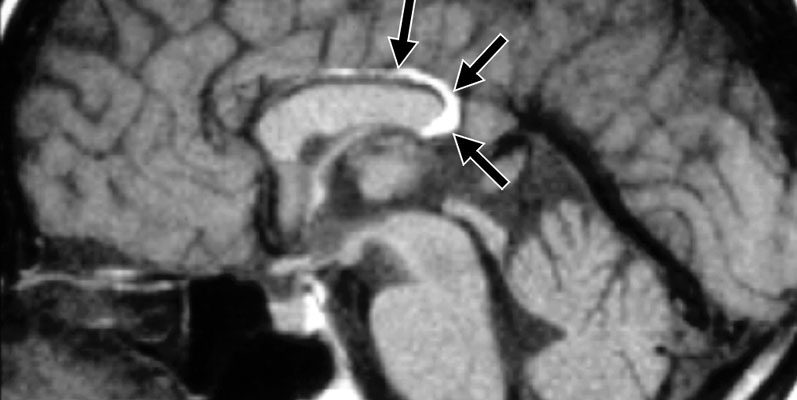

Этот диагноз не редкий. Около 25% пациентов, имеющих тест на магнитн о-резонансную томографию, показывают его в результатах исследования. О чем именно этот диагноз? Человеческий мозг покрыт тремя слоями менингов: жесткая шина, аракноида и мягкая мембрана. Под аракноидальным покровом находятся жидкие пространства, в которых цирброспинальная жидкость циркулирует (центр жидкости, окружающий мозг). Прозрачный раздел состоит из двух тонких церебральных пластин, которые разделены зазором между передней частью и аркой мозжечка. Киста перегородки представляет собой своего рода паучья киста, в которой жидкость накапливается между бляшками прозрачной перегородки для мозга.

Самую ГЧП находится на высоте углах передних боковых желудочков мозга, а его разгибание на заднюю часть боковых желудочков выделяется как полость Верге. Во время развития эмбриона эта полость закрывается сзади и спереди, поэтому остаток полости Верге в закрытом PPT намного реже.

- МРТ является одним из наиболее показательных методов диагностики. Исследование выявляет все патологические изменения, которые происходят в прозрачной перегородке. Расположение кисты, его диаметр и структура объясняются;